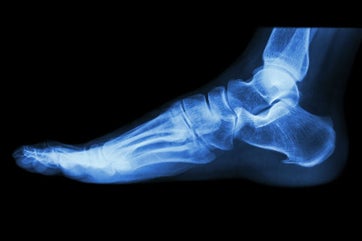

Souvent, on parle à tort d'épine calcanéenne, car elle n'est pas la cause de la douleur, mais une conséquence. Il s'agit en réalité d'une calcification progressive du tendon à son point d'insertion, visible à la radio mais n'étant pas toujours présente ni corrélée à l'intensité de la douleur. Le diagnostic est avant tout clinique.